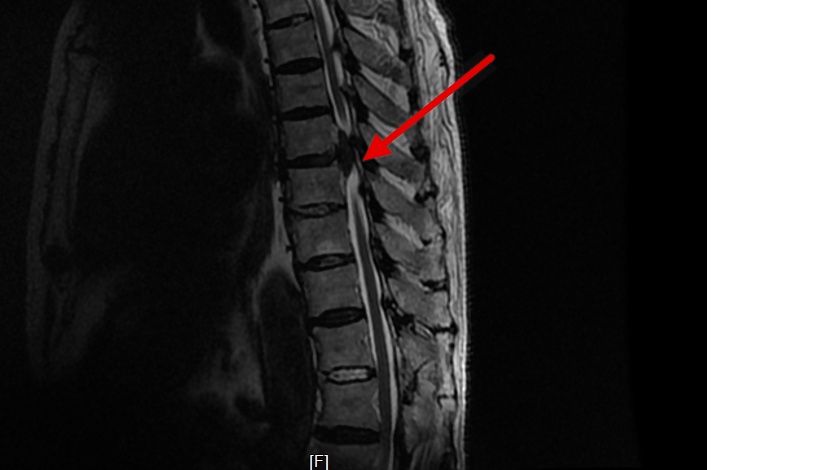

来自大连的张大爷(化名)备受颈椎病的折磨,左上肢麻木疼痛难忍,去过好几家医院都说让开放手术,张大爷很恐惧,经多方打听了解到我们医院能做微创手术就来我院就诊,我们给他做了颈椎椎间孔镜手术。

术后患者症状明显减轻,张大爷终于可以睡个好觉了。